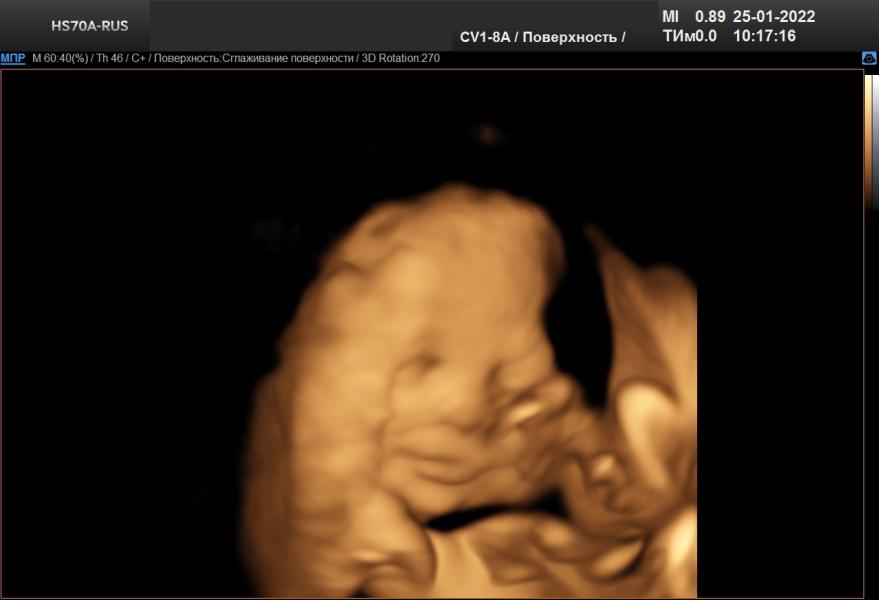

Поздравляю всех Татьян, Танечек, Танюшек с днём ангела. Ну а саму себя ещё и с началом декрета💃💃💃Дождалась🤣🤣🤣И начался он прекрасно, с утра ездила на УЗИ, увидела моего маленького мальчишку🧒🧒🧒Всё с ним хорошо, соответствует по размерам 31.1 неделям, весит 1713 грамм. Улыбался, открывал глазки💙💙💙Мы ждём тебя родной наш сынок❤❤⚘